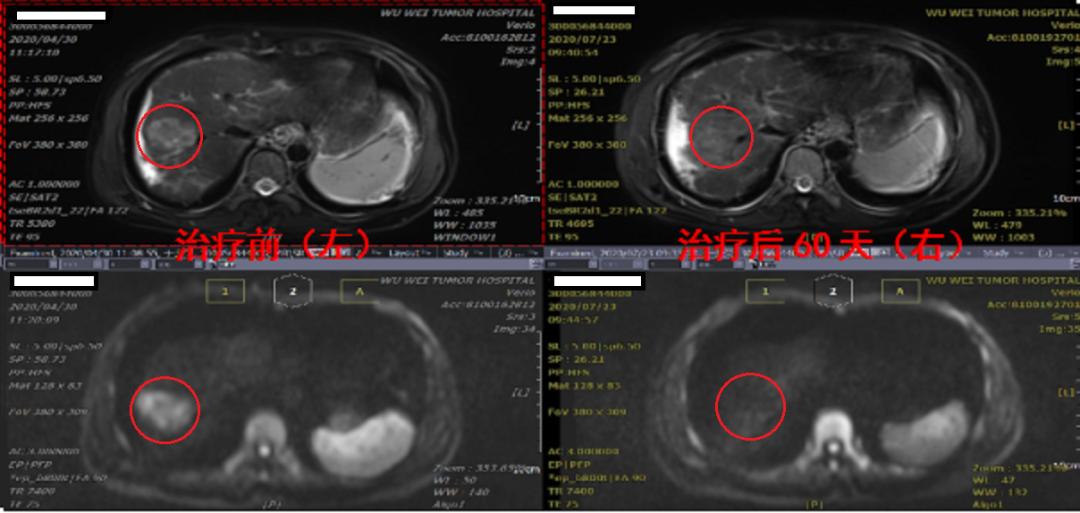

我中心第一例肝癌治疗后满2月了

肿瘤完全消失!

治疗前上腹部核磁提示肝癌位于肝S8段,大小约5cm,查肝癌肿瘤标志物AFP为1525 IU/mL。于女士接受了我中心肝癌重离子放射治疗,治疗疗程6次,全程无痛苦。现已完成治疗2个月后行复查,神奇的疗效出现了,肿瘤基本上完全消失,弥散成像完全恢复正常,肿瘤标志物AFP降至140 IU/mL,如此好的疗效让一个痛苦的家庭重新获得的希望,让背负巨大压力的灵魂焕发了新生。这样活生生的例子正是我中心日常工作中的点点滴滴。